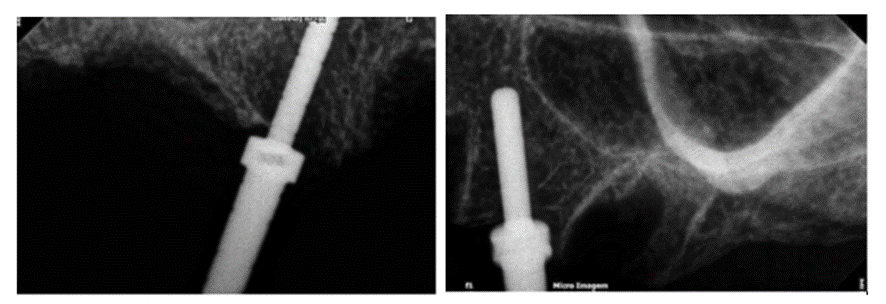

Foram planejados quatro implantes com distribuição biomecânica, segundo o polígono de Roy, de acordo com as radiografias transoperatórias abaixo.